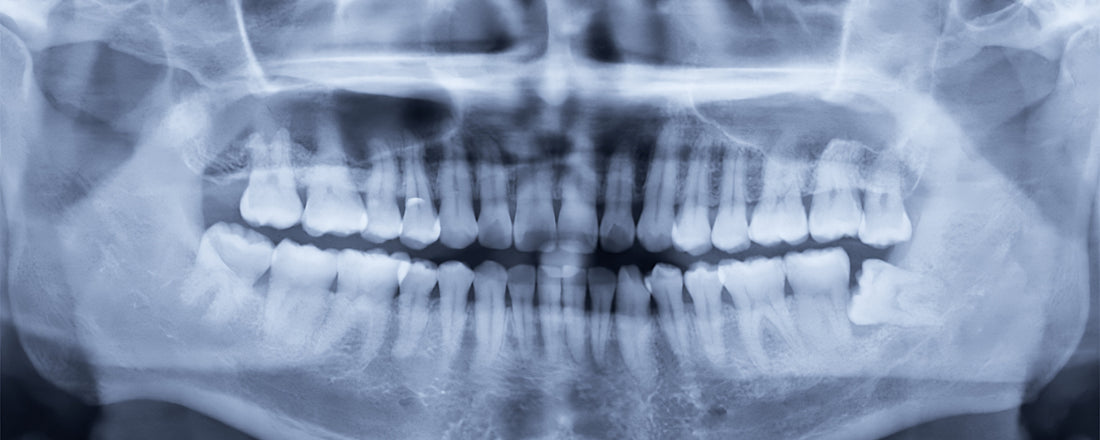

Obrázok 12: Horná čelusť. Všimnite si vertikálny šev (pripomínajúci "prasklinu") naprieč hornou čelusťou. Je to spojenie medzi časťami kosti, ktoré umožňuje určitú flexibilitu rastu čeluste. Podobné švy máme aj na lebke. Umožňujú jej rast počas dospievania.